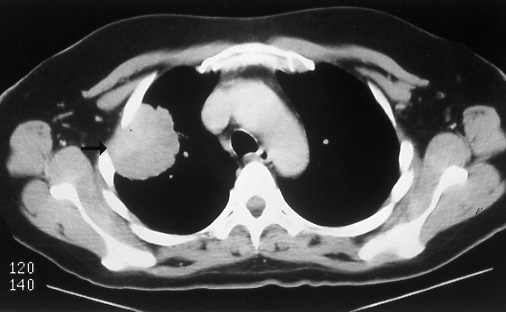

Fig. 41b: Computed tomographic scan of the lesion (Fig. 41a) showing chest wall invasion (arrow). The lymph nodes were free of disease, T3 N0 M0, stage IIB.